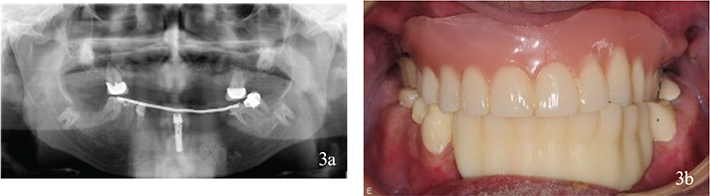

Figure 4

Figure 4. (a, b) Status after treatment.

Six implants in the maxillae and four implants in the mandible (Astra Tech Implant System® Osseospeed® TX, Dentsply Sirona, Mölndal, Sweden) were provided with implant screw-retained fixed partial dentures with metal base and angulated screw channels (Heraeus Dental AB, Biomain®, Helsingborg, Sweden) on Uniabutments (Dentsply Sirona, Mölndal, Sweden). Teeth were restored with fixed dental prosthesis.

The patient was lost to follow-up for 3 years after dental treatment, but then returned to the specialist Prosthodontics Clinic for regular follow-ups. Eight years after dental treatment, two teeth had been endodontically treated, an upper molar had a distobuccal root removed, and one dental implant had been lost in the mandible. The implant-retained fixed partial denture (FPD) was modified accordingly (Figure 5a, b).

Figure 5. (a, b) Complications 8 years after treatment.

Two teeth were endodontically treated. The distobuccal root on a molar in the maxillae had been resected. One implant in the mandible was lost because of loss of bone integration, and the fixed partial dentures was adjusted after the implant loss.